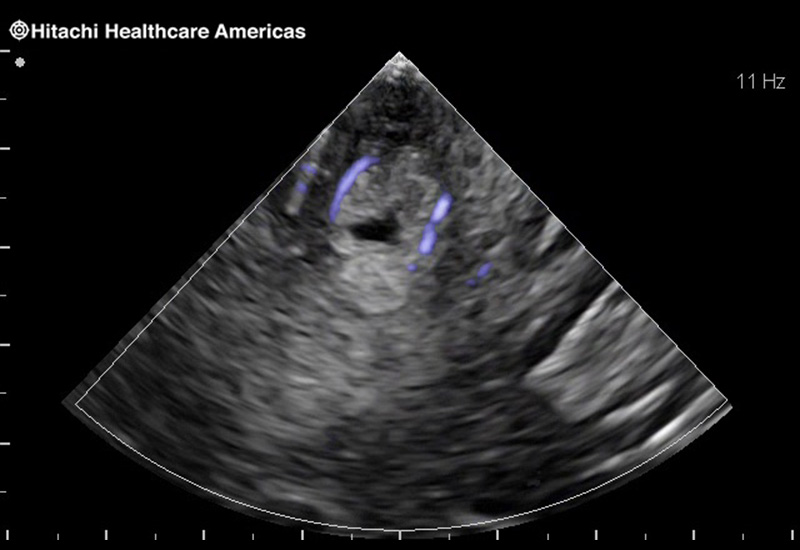

Superior guidance for all applications

Fujifilm Healthcare Americas is committed to designing tools that help surgeons navigate inside the human body and provide the necessary information to immediately make critical surgical decisions.

Fujifilm Healthcare's dedication to Surgeons provides outstanding ultrasound technology, professional support and the specialized tools necessary to best perform comprehensive real-time ultrasound imaging in Breast Surgery, General Surgery, Laparoscopic Surgery, Neurosurgery, Robotic Surgery and Surgical Oncology.

Recognized for our outstanding image quality, outstanding system reliability and intuitive use of cutting edge technology, Fujifilm Healthcare remains the standard in the field of Surgery.

Recognized for our outstanding image quality, outstanding system reliability and intuitive use of cutting edge technology, Fujifilm Healthcare remains the standard in the field of Surgery.